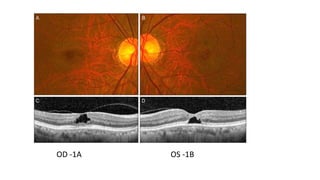

OD -1A OS -1B

Clinical features